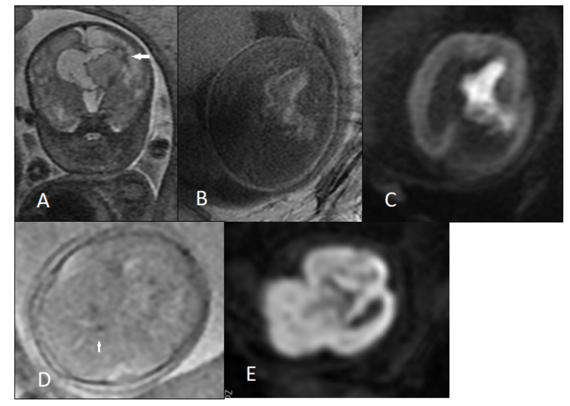

Figure 1. An 18 weeks fetus with mild ventriculomegaly and suspected corpus callosum abnormality was referred for fetal MRI. A, B, C) T2-weighted MRI images showed complete agenesis of corpus callosum and unilateral abnormal sulcation(arrow) in occipital horn. D, E) Transvaginal neurosonography found similar findings.

Participating women had a history of previous pregnancies with CNS anomalies or were pregnant with fetuses suspected of having brain abnormalities on a recent screening ultrasound exam. Investigated fetuses underwent karyotyping and were tested for TORCH infections. All study subjects underwent MRI one to two weeks after the ultrasound exam, and transvaginal NSG was undertaken within one week after MRI for all of the investigated fetuses. Based on the US-MRI concordancy, subjects were divided into four subgroups: (a) the MRI/NSG findings confirmed the US findings; (b) the MRI/NSG findings supplemented the US findings (Figure 1); (c) the MRI/NSG findings contradicted the initial US impression; and (d) the MRI/NSG findings ruled out the initial US diagnosis (false positive US).

Brain US, NSG, and MRI findings showed a significantly high level of concordance. Most common CNS pathologies found in all imaging modalities concordantly were ventriculomegaly (48.6%), intracranial hemorrhages (12.9%), corpus callosum anomalies (11.4%), and cortical malformation (13.5%). As Table 2 shows, among cases whose brain US was discordant with NSG/MRI, 73.2% had additional findings in NSG/MRI (Figure 1), 23.9% were diagnosed with other brain anomalies, and 2.8% showed a normal brain in NSG/MRI (false positive US). The US exams performed after the 20th week of pregnancy showed a significantly higher concordancy with NSG/MRI, and diagnosed brain abnormalities with a higher accuracy (Figure 3). Generally, 54.9% of cases whose brain US was discordant with NSG/MRI showed similar findings in NSG and MRI (Table 2).